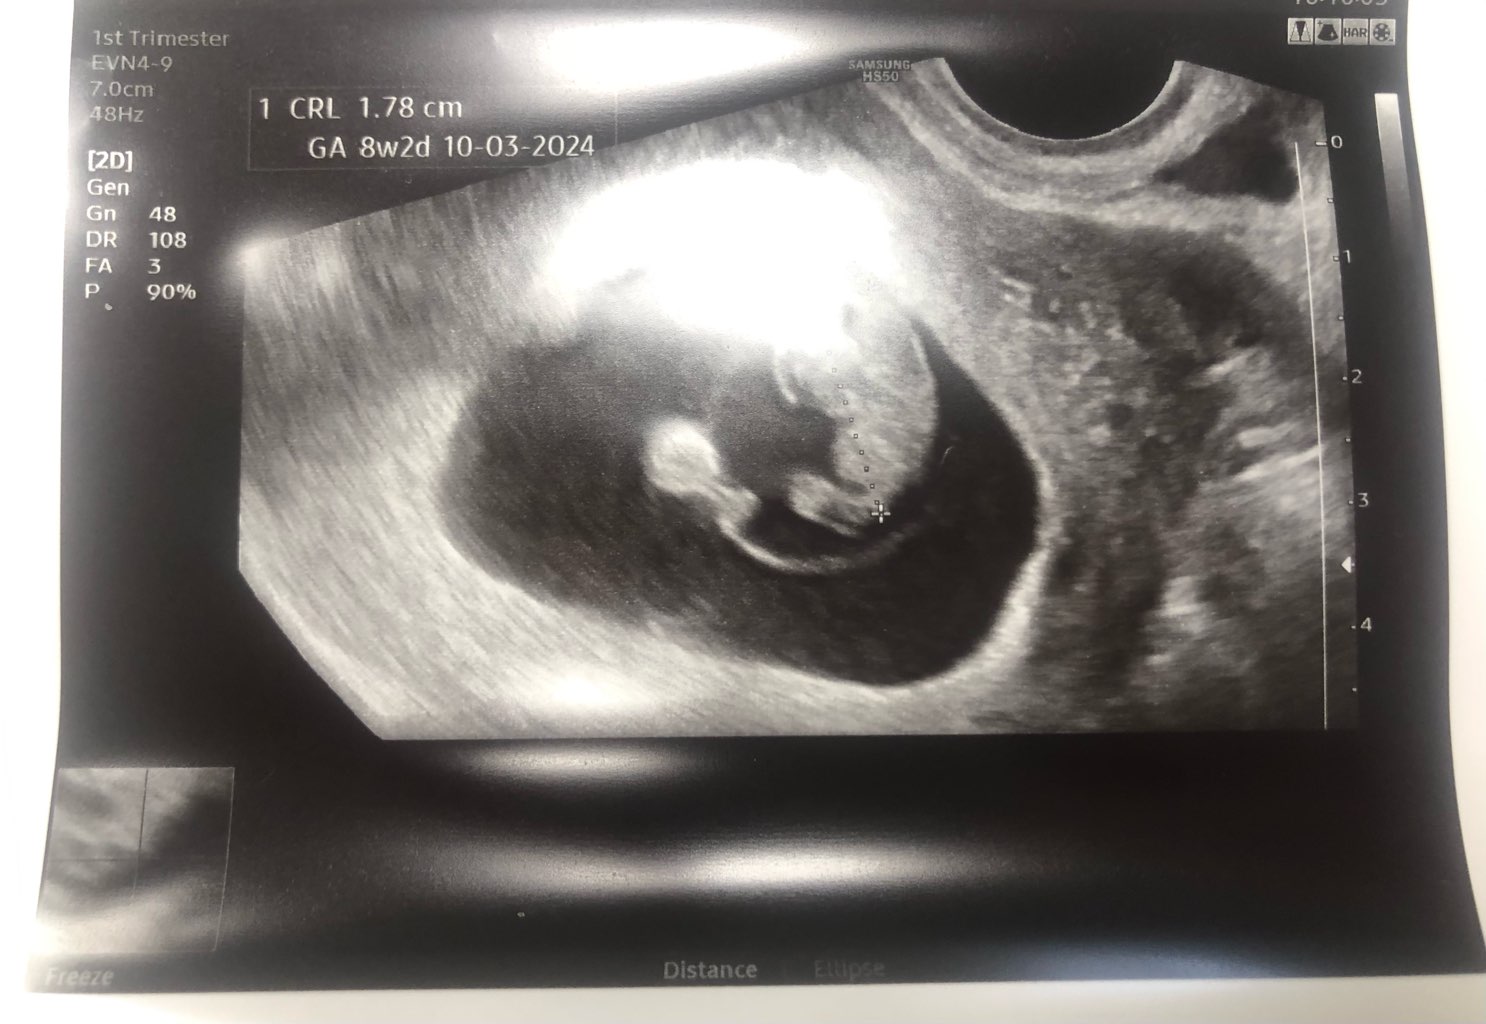

ale diabeł tkwi w szczegółach - najpierw robi się biopsję kosmówki, żeby sprawdzić czy dziecko nie jest zakażone. Następnie można to leczenie prewencyjne włączyć. Leczyć już zakażone dziecko w okresie prenatalnym też można tzn zminimalizować skutki działania wirusa, ale to ma sens w drugim, trzecim trymestrze wg informacji jakie zebrałam. Bo jak wiadomo w pierwszym to już "nie ma czego zbierać"

może w DE znajdą jakieś rozwiązanie dla mnie... Spróbuję załatwić jakaś wizytę koło 20 sierpnia, najlepiej byłoby mi dowiedzieć się czym prędzej czy przekazałam chorobę czy nie. Jeśli tak to wiadomo... Lepiej nie ryzykować z czekaniem i złudną nadzieją, żeby się nie skończyło bardziej traumatycznymi przeżyciami